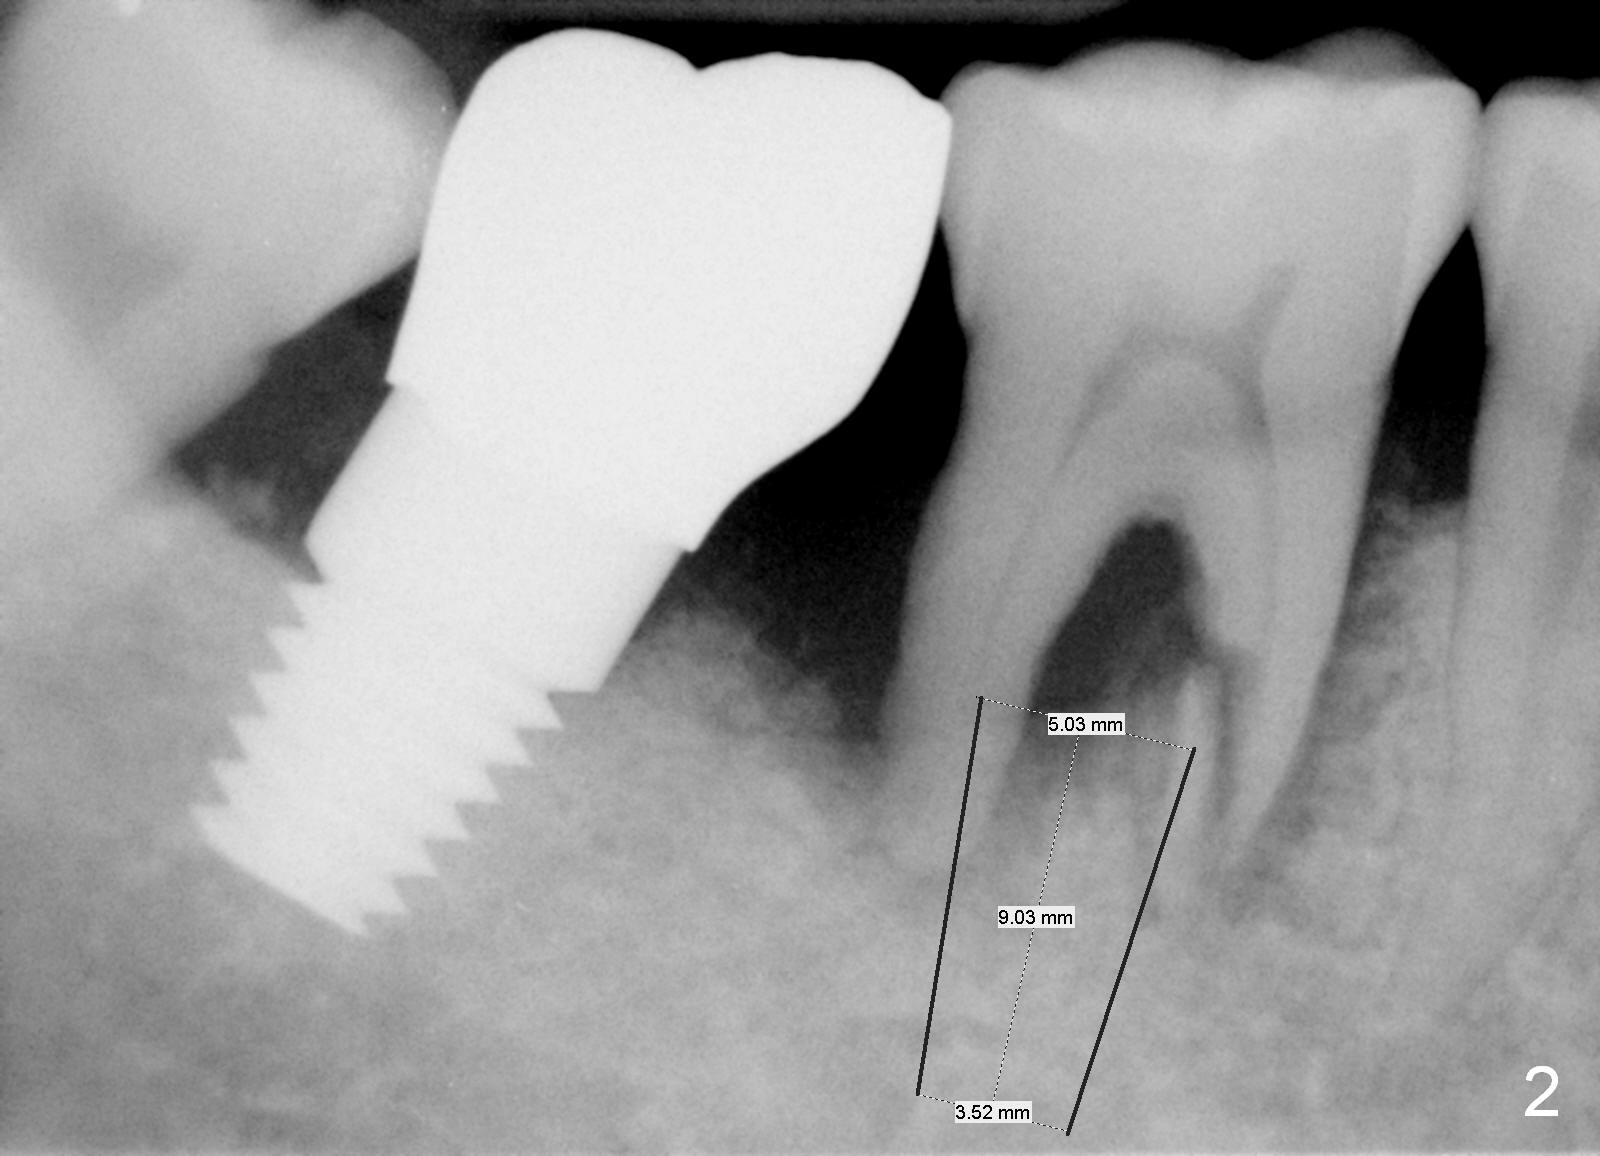

A 64-year-old man has pain at night, possibly associated with vertical fracture of the mesial root of the tooth #30, 1.5 years post cementation at #31 (Fig.1,2 (2 weeks post #7 implant placement). After extraction without antibiotic socket treatment, use medium Rongeur to even the irregular septal crest (Fig.3 red line) prior to using 1.6 mm pilot drill. The initial depth will be 13 mm. PA will be taken to confirm the apical position relative to the Inferior Alveolar Canal. An implant is placed at the distal and septal crestal level with bone graft in the distal socket, while the implant is well below the the mesial crest. The implant should be not too big. Make sure that the larger abutment does not touch the mesial crest. Since the entrance to the mesial socket is smaller than that of the distal, bone graft is placed in the mesial socket prior to abutment placement.